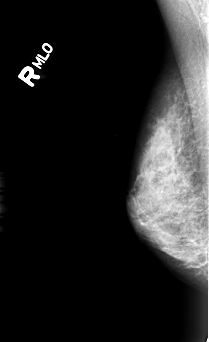

B_3005_1.RIGHT_MLO

RIGHT_CC LINES 4456 PIXELS_PER_LINE 2696 BITS_PER_PIXEL 12 RESOLUTION 50 NON_OVERLAY

RIGHT_MLO LINES 4440 PIXELS_PER_LINE 2712 BITS_PER_PIXEL 12 RESOLUTION 50 NON_OVERLAY